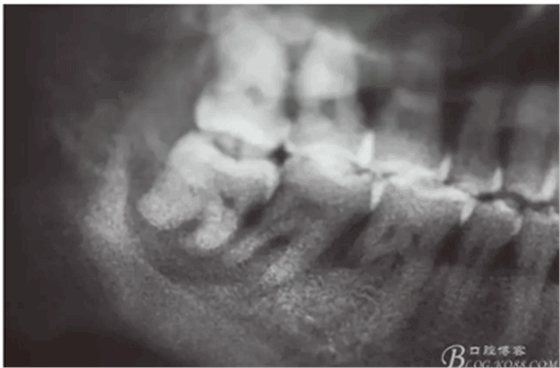

圖2.局部的放大影像情況。48骨質(zhì)吸收至下頜管邊緣,陰影范圍廣,拔除48后牙槽窩處理要小心。